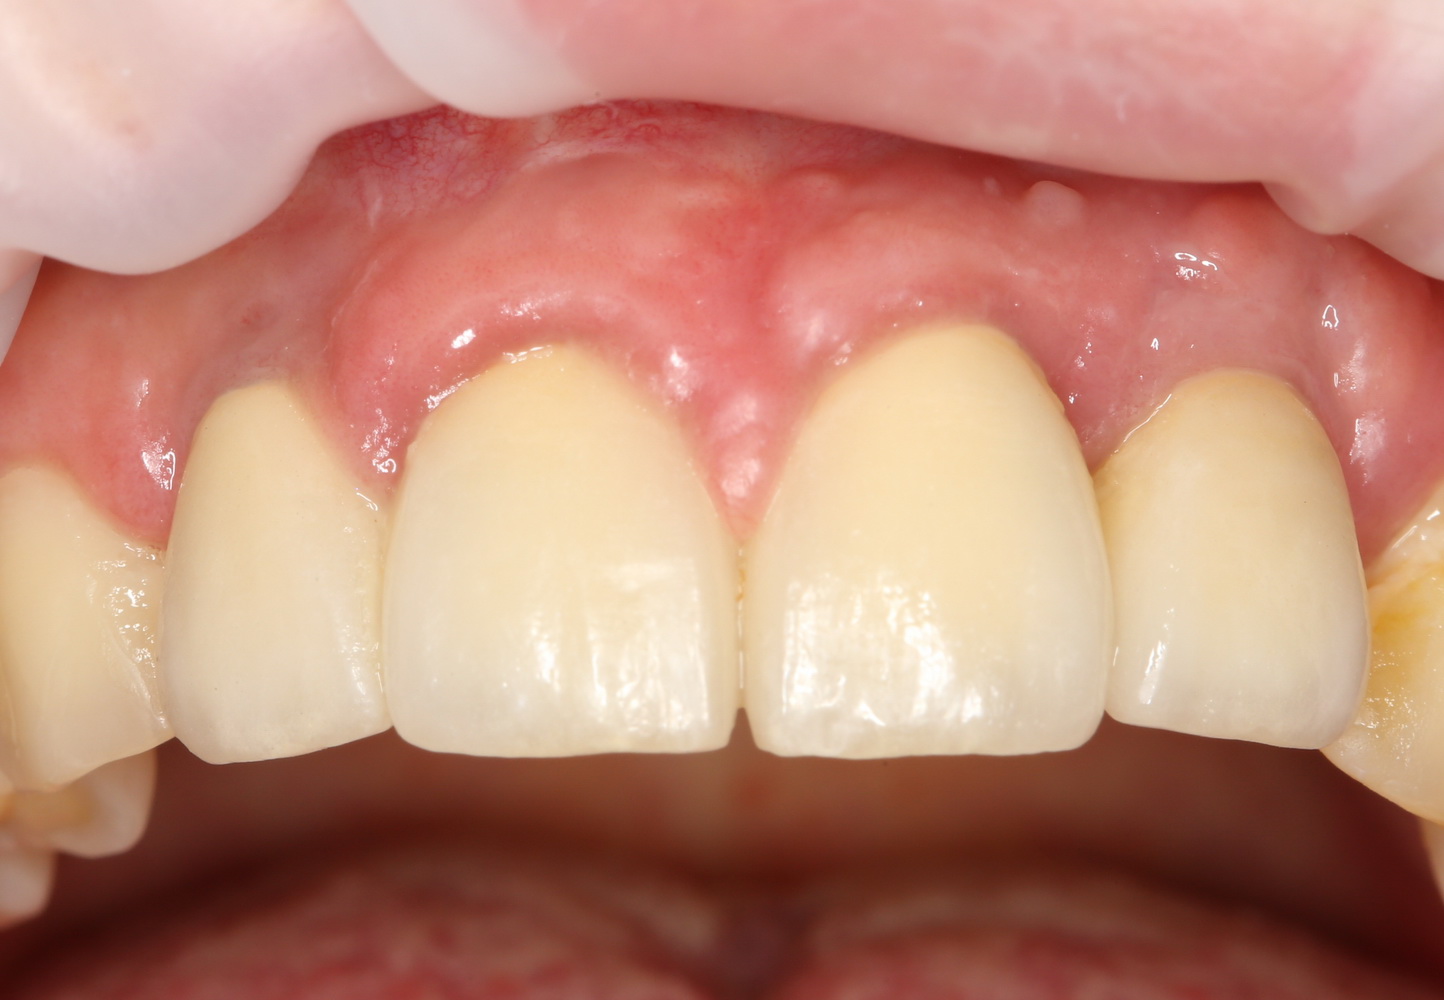

Вот фотография, сделанная на одном из профилактических осмотров, примерно через полгода после завершения протезирования:

Сравните это с тем, что было ранее.

Прошло еще полгода:

Есть проблемы с гигиеной, это да. Но, на мой взгляд, мы добились того, чего желала пациентка — естественного вида фронтальной группы зубов.